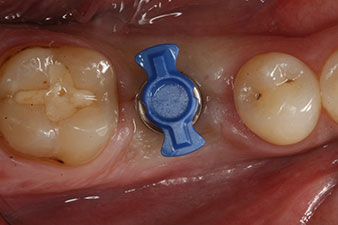

Después de la cicatrización de los tejidos blandos, se volvió a determinar la estabilidad del implante antes de continuar con el tratamiento protésico.

Los dos valores eran prácticamente idénticos y se encontraban en la transición del área media a la alta; en este punto cabe reseñar que el valor más bajo sirve siempre como referencia para establecer el tratamiento adecuado.

Con ello, fue posible documentar una correcta osteointegración y una estabilidad biológica suficiente, lo que permitió realizar una conformación en la misma sesión.